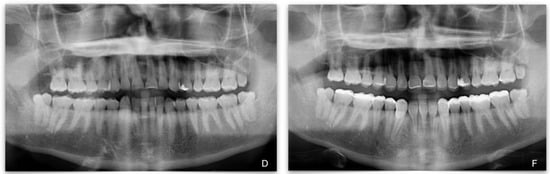

Total Rehabilitation Using Adhesive Dental Restorations in Patients with Severe Tooth Wear: A 5-Year Retrospective Case Series Study

3. Results